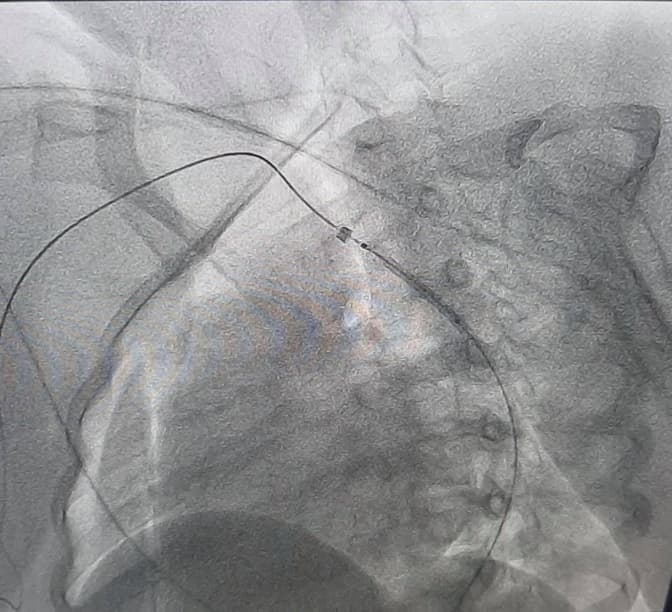

У Львівській клінічній лікарні швидкої медичної допомоги у центрі серця і судин вперше в Україні провели операцію за допомогою передопераційного моделювання методикою віртуальної реальності. Про повідомили на Фейсбук-сторінці лікарні.

За словами медиків, у дівчинки виявили вроджену ваду серця під час обстеження. У неї була коарктація аорти, що означає звуження головної артерії кровоносної системи, внаслідок чого підвищується тиск у верхній частині тіла.

Вроджену ваду медикам вдалося ліквідувати за допомогою сучасної методики віртуальної реконструкції анатомії аорти і її гілок. Лікарі провели оперативне втручання, встановивши дівчинці стент у просвіт судини.

«Результат лікування не забарився й одразу після оперативного втручання у дитини нормалізувався артеріальний тиск, а також зникла різниця тиску між верхніми та нижніми кінцівками», – зазначили у лікарні.

Фото Клінічної лікарні швидкої медичної допомоги